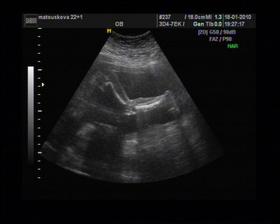

8/10 jsme se byli podívat u paní doktorky, zda testy nelhaly - a ono n e. Puclík měřil 0,37cm a co je důležité - srdíčko už funguje. Táta s Pepínem byli v ordinaci s námi, a když se na monitoru objevilo mimi, tak ho Pepíno pozdravil - udělal mu "ahoj" 🙂 oba nás to s Honzou dojalo. Další kontrola 22/10.